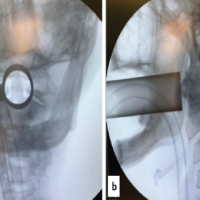

Patient was operated under brachial block and sedation. She was placed in the right lateral decubitus position with elbow support such that the forearm was dangling free, and the elbow was in 90° flexion. Overall reduction with mild traction was checked by the C-arm in anteroposterior and lateral views. A posterior midline incision proximally from the level of deltoid insertion to distally along the lateral supracondylar ridge (approx 18–20 cm long) was made. Skin, subcutaneous tissue, and deep fascia were cut to expose the triceps muscle, and hemostasis was achieved. Proximally, the interval between lateral and long head of triceps was identified and dissected to find the radial nerve with its vena comitans and profunda brachii artery (Fig. 2). The entire neurovascular bundle with its sheath was elevated from the posterior surface of the humerus using a blunt and curved periosteal elevator. Distally, the triceps were split along the lateral pillar of distal humerus. Olecranon fossa was identified. With a blunt and narrow periosteal elevator, a submuscular tunnel between the posterior surface of the humerus and the triceps muscle was created very carefully so as not to displace any of the comminuted fragments. Extra-articular anatomical titanium 3.5 mm, 10-hole plate specific for the left side was slid in the tunnel underneath the radial neurovascular bundle under fluoroscopic guidance. With mild traction, acceptable reduction was achieved and confirmed under image-intensifying television with both views. Preliminary K-wires through the plate and a 3.5 mm cortex screw proximally and distally were fixed. Reduction was again confirmed and further locking screws were fixed. A total of 7 screws (3 proximal and 4 distal) were fixed and stability in flexion, extension as well as varus, and valgus was confirmed. Normal saline wash, meticulous hemostasis, and muscle closure with 1–0 vicryl was done (Fig. 3). This was followed by subcutaneous and skin closure in layers. Sterile well-padded dressing was applied, and the arm was immobilized in a pouch arm sling. Post-operative X-ray is shown in Fig. 4.